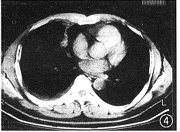

图5 肺窗:右肺门部不规则高密度肿块,大小28 mm×40 mm,CT值68.7 HU,病灶前方邻近外侧隐约见少许散在小点状高密度灶

图6为图5纵隔窗:右中叶支气管壁增厚,管腔略窄

图7 为图5纵隔窗:分歧下淋巴结肿大,短径为20 cm。术前诊断:右侧中央型肺癌,纵隔淋巴结转移;术后病理诊断:干酪增殖性肺结核

图1 肺窗:右肺下叶背段胸膜下孤立结节,直径2 cm,边缘毛糙,CT值54 HU,病灶与胸膜间见多条线影

图2 为图1纵隔窗:病灶密度均匀,边缘光滑。术前诊断:周围型肺癌;术后病理诊断:干酪增殖性肺结核

3.肺门及纵隔淋巴结增大:2例(图5~7),1例表现为血管前、左侧主动脉弓旁支气管分歧下及左肺门淋巴结均增大,并融合成巨块状。另1例表现为右肺门及支气管分歧下淋巴结增大,尤以右肺门淋巴结增大为明显。这2例中1例 22岁,另1例 66岁。